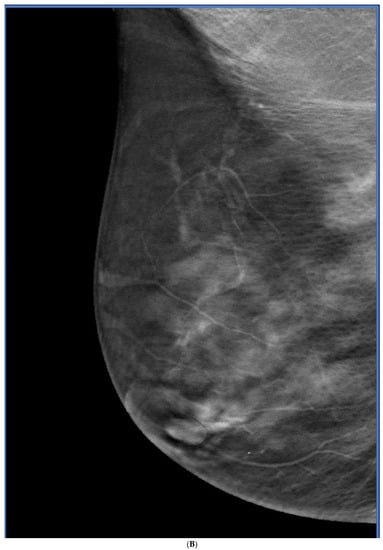

8. Contrast-Enhanced Mammography (CEM)